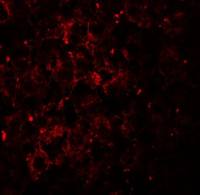

Immunohistochemical analysis of paraffin-embedded human colon carcinoma, using Lhx4(GTX118105) antibody at 1:250 dilution.

Antigen Retrieval: Trilogy™ (EDTA based, pH 8.0) buffer, 15min